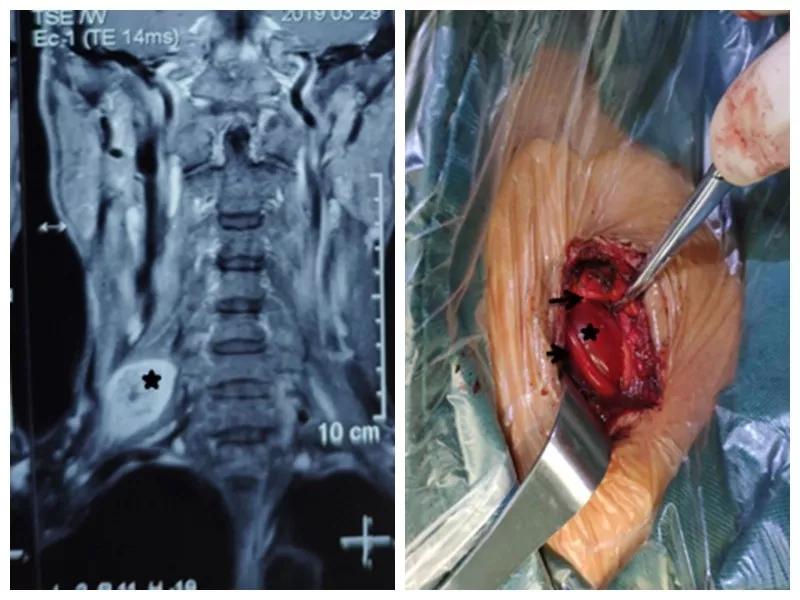

家住户县的王师傅一年前无意中发现右颈部长了一个“包”,当时并未在意,但是他发现这个“包”逐渐增大,并且伴有压痛,按压这个“包”时还可引起右胳膊疼痛,在当地医院就诊,未见好转,在我市某三甲医院检查及包块穿刺活检示右侧颈部神经鞘瘤,医生告诉他可以手术切除,但是风险很大。王师傅慕名来到91论坛 骨一科就诊,严少荣主任接诊后立即安排住院治疗,并安排由西安市手外科常委王涛主任医师及主治医师张磊组成治疗小组。积极进行术前检查,发现右颈部肿瘤有3×3×3 cm大小活动性差的肿瘤。并有触电样感觉向肢体放射。经过制定缜密手术方案,严主任细心耐心告知患者手术的风险性,并安排术中神经电生理监测,提高手术安全性,由王涛主任医师、张磊主治医师和麻醉医师李楠及手术护士组成手术团队,在全麻下行右侧颈部神经鞘瘤切除术,术中发现此神经鞘膜瘤巨大,位于臂丛神经上干并包饶颈5.6神经,与周围组织黏连严重,由于该肿瘤起源于神经根纤维许旺氏细胞,遂着肿瘤不断生长,将神经干内正常神经纤维挤向肿瘤四周,包含在神经外膜内形成肿瘤的“包膜”呈鱼肉样。王涛主任医师在仔细保护神经的情况下采用“层层剥离挤出法”将肿瘤取除,避免了误将含正常神经纤维的“包膜”随肿瘤一起切除,造成神经干损伤及缺失,从而造成上肢功能的不可逆障碍的悲剧。术后经过主管护士解妍及全体医护人员的精心治疗护理,王师傅原有神经压迫症状消失,无任何感觉运动异常,术后再次病检符合神经鞘瘤。王师傅满意出院。

通过此例罕见臂丛神经上干神经鞘瘤病人治疗,标志着我科在高位臂丛神经干手术达到一个新高度。